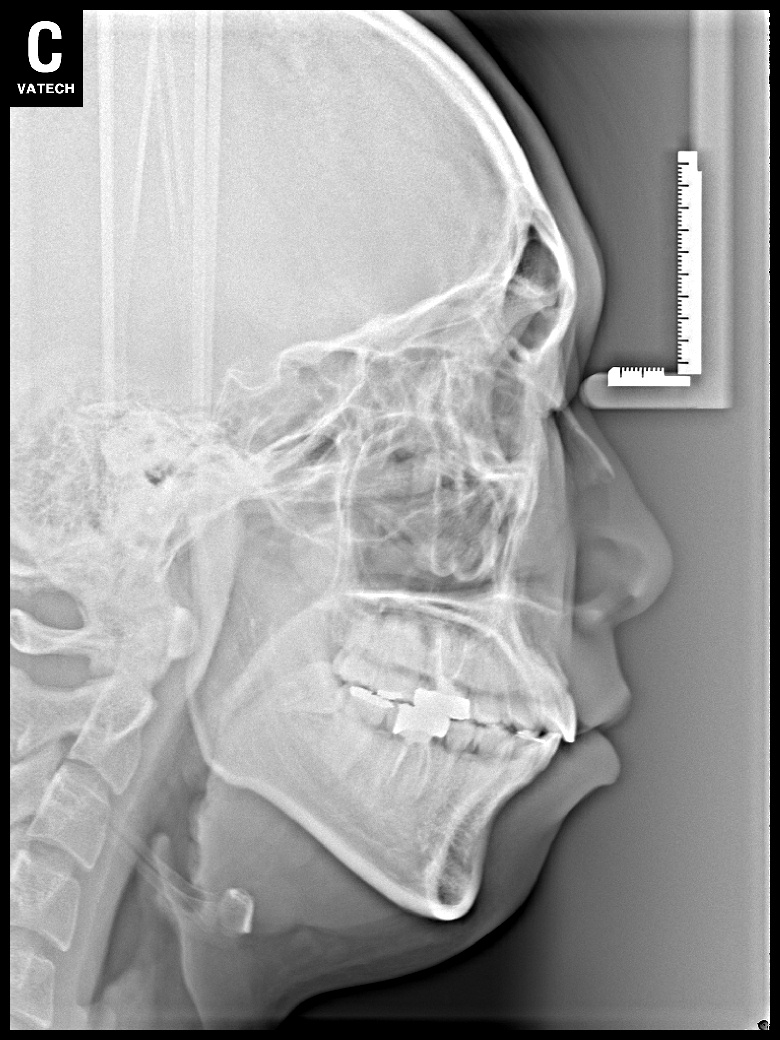

치료 후 사진입니다.